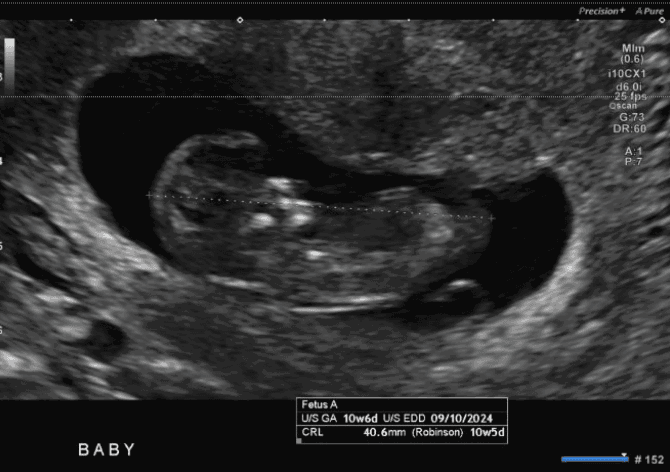

The crown-rump length (CRL) is a measurement of the embryo from the top of the head (crown) to the bottom of the buttocks (rump). This measurement is most accurate between 7 and 13 weeks of gestation, when the embryo is still too small to accurately measure other anatomical features.

During an early pregnancy ultrasound, a trained healthcare professional will use a transducer to create ultrasound images of the embryo. The transducer emits sound waves that bounce off the baby and internal structures, creating an image on the screen. The healthcare professional will then use calipers on the ultrasound screen to measure the CRL.